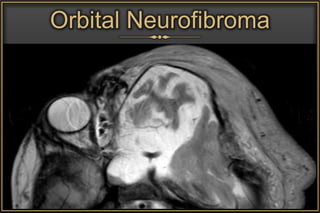

Orbital Neurofibroma